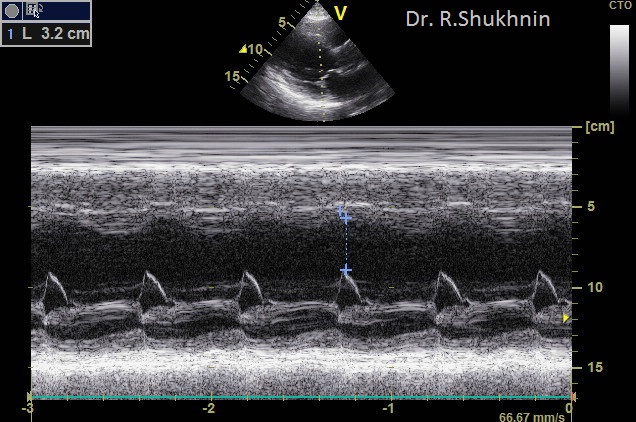

На фото из практики д-ра Шухнина Р.Е.

1) Эхокардиограмма, М-режим демонстрирует резкое расширение левого желудочка сердца при дилатационной кардиомиопатии – пока неизлечимого заболевания сердца. Сердечная недостаточность – одна из причин отеков.